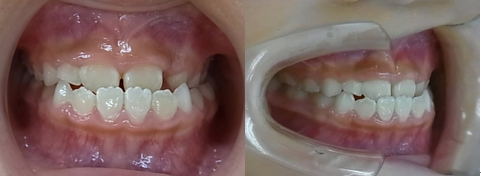

☆上顎から矯正装置を装着していきます。

☆上顎の歯が揃ってから、下額に矯正装置(ブラケット)を装着します。

☆終了時(1年6ヶ月)